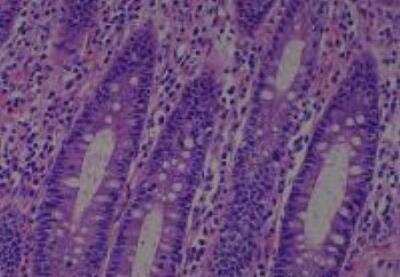

Hematoxylin & Eosin Stain: Human Common Tissue MicroArray (Normal Adjacent) [NBP2-30215] - 01. Stomach